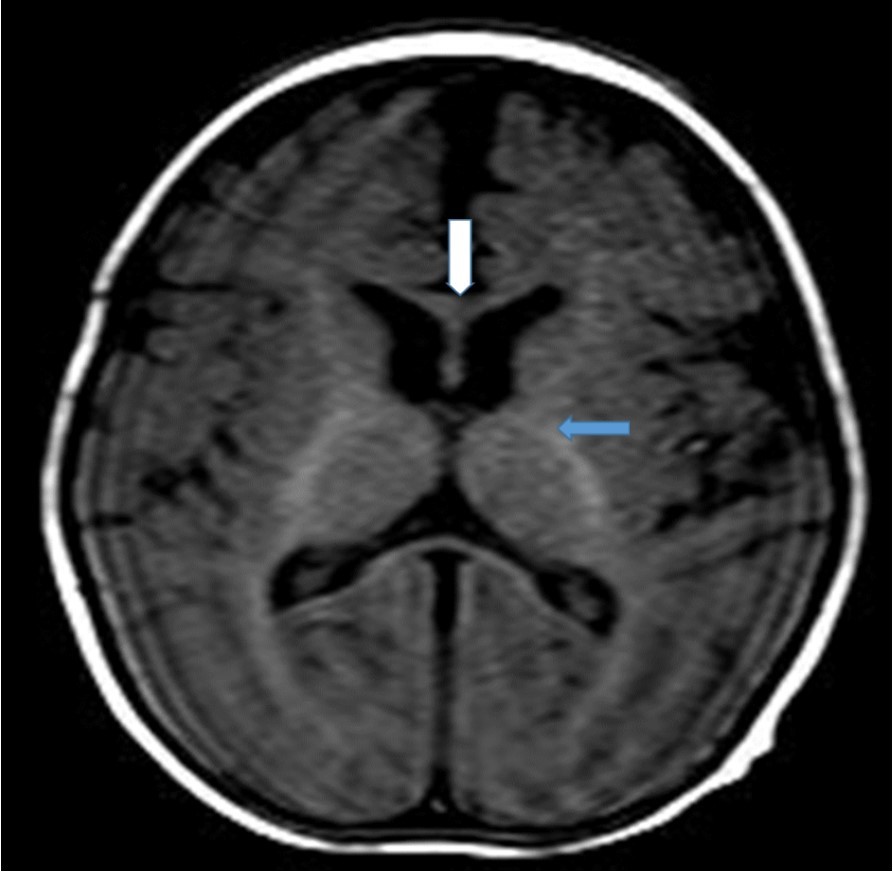

Cranial magnetic resonance imaging (MRI) was requested owing to the patient’s convulsion history and retarded development. The cranial MRI showed diffuse hypoplasia of the corpus callosum in the midline sagittal T2-weighted image (Figure 1 white arrow). T1-weighted imaging showed hypointensity due to delayed myelination of the genu of the corpus callosum (Figure 2, white arrow), which should normally appear hyperintense like the posterior limb of the internal capsule (Figure 2, blue arrow).

Figure 2.T1-weighted magnetic resonance image of the patient (7-month-old girl). The genu of the corpus callosum is hypointense due to myelination delay. In this age group, the genu of the corpus callosum should become hyperintense similar to the posterior limb of the internal capsule (blue arrow) due to myelination.